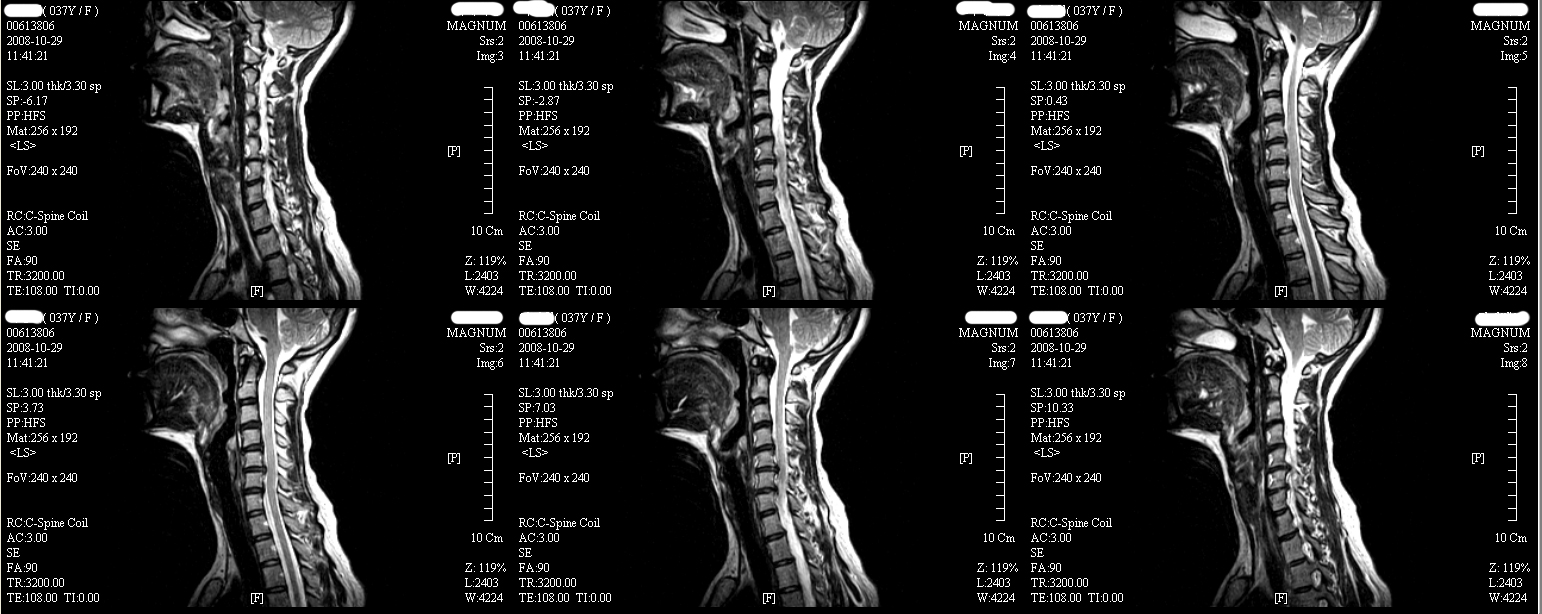

̿ ؾ ũ ڸ Ŀ MRI 캸 http://3wboard.zicoree.com/New_Board/Board/Read.php?Board=compill-50-free1&No=3401 ---------------------- ı ι° no 3426 date 2008-12-06 20:07:35 hits 35 name ̿ (sorogi@hitel.net) IP: 125.134.214.75 Ǿµ. ÷ ȣǴٰ ٽ ȭǴ ݺߴµ ȭȭ Ȯ Ǿϴ. ű Ŀ̶ ʹ ʹµ Բ ùٸ Գ̷ ϸ ϳ °ſ. ʿ κ ִϴ ڸ ߿伺 ٽ Ҵϴ. Ẹø ȸ ø Ͼ. ߿ ܿ ñ ٶϴ. http://3wboard.zicoree.com/New_Board/Board/Read.php?Page=1&dummy=1228861813&Board=compill-50-free1&No=3426&Search=&keyword=&period=10000 |